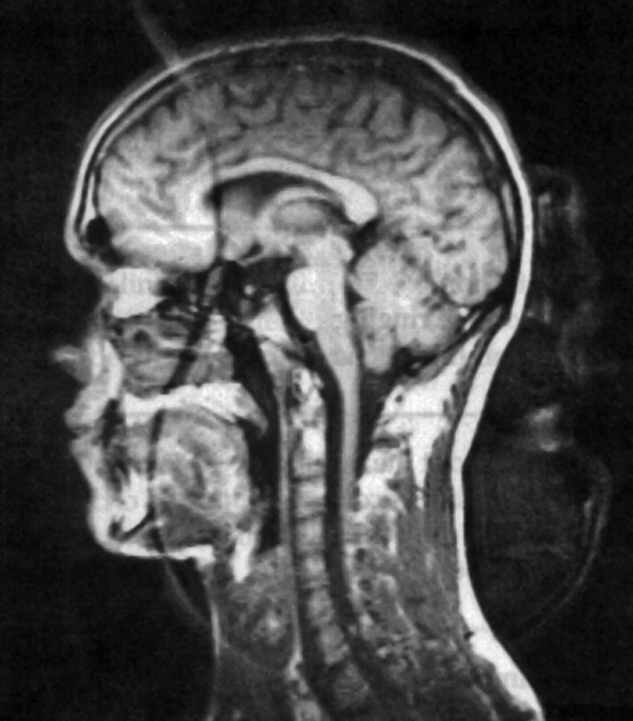

Figure 17-13:

Truncation artifacts.

Top: (a) 60% acquisition with ar­tifacts. (b): 80% acquisition, no artifacts visible.

Bottom: Truncation artifact mimicking sy­ringo-myelia. (c) T1-weighted, (d) T2-weighted im­age.